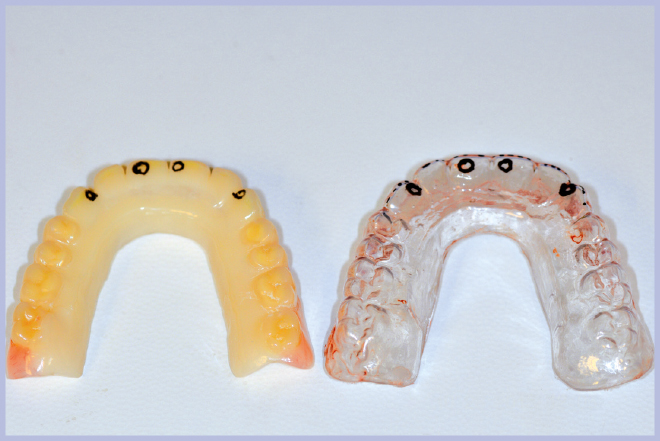

Quindi, con l’ausilio di una mascherina in resina trasparente, si è effettuata la registrazione occlusale; la mascherina è stata sfruttata anche per la demarcazione dei punti della nuova protesi da scartare in corrispondenza della posizione delle cappette (Figg. 7, 8).

- Fig. 7 – Mascherina in resina per la registrazione occlusale

- Fig. 8 – Demarcazione della posizione delle cappette sia sulla mascherina che sulla nuova protesi